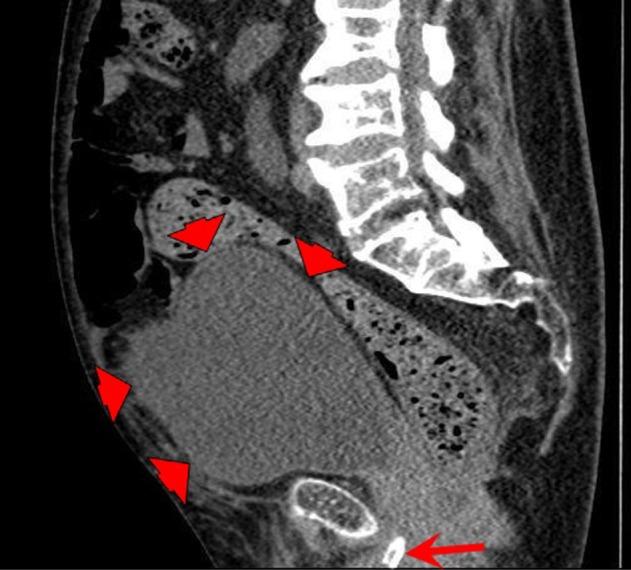

A male tetraplegic patient attended accident and emergency with a blocked catheter; on removing the catheter, he passed bloody urine. After three unsuccessful attempts were made to insert a catheter by nursing staff, a junior doctor inserted a three-way Foley catheter with a 30-mL balloon but inflated the balloon with 10 mL of water to commence the bladder irrigation. The creatinine level was mostly 19 µmol/L (range: 0-135 µmol/L) but increased to 46 µmol/L on day 7. Computerized tomography urogram revealed that the bilateral hydronephrosis with hydroureter was extended down to urinary bladder, the bladder was distended, prostatic urethra was dilated and filled with urine, and although the balloon of Foley catheter was not seen in the bladder, the tip of the catheter was seen lying in the urethra. Following the re-catheterization, the creatinine level decreased to 21 µmol/L. A follow-up ultrasound scan revealed no evidence of hydronephrosis in both kidneys. Flexible cystoscopy revealed inflamed bladder mucosa, catheter reaction, and tiny stones. There was no bladder tumor. This case report concludes that the cause of bilateral hydronephrosis, hydroureter, and distended bladder was inadequate drainage of urinary bladder as the Foley balloon that was under-filled slipped into the urethra resulting in an obstruction to urine flow. Urethral catheterization in tetraplegic patients should be performed by senior, experienced staff in order to avoid trauma and incorrect positioning. Tetraplegic subjects with decreased muscle mass have low creatinine level. Increase in creatinine level (>1.5 times the basal level) indicates acute kidney injury, although peak creatinine level may still be within laboratory reference range. While scanning the urinary tract of spinal cord injury patients with indwelling urinary catheter, if Foley balloon is not seen within the bladder, urethra should be scanned to locate the Foley balloon.

一名男性四肢瘫痪患者因导尿管堵塞前往急诊;拔除导尿管后,他排出了血尿。护理人员三次尝试插入导尿管均未成功,一名初级医生插入了一根带30毫升球囊的三腔Foley导尿管,但仅用10毫升水充盈球囊以开始膀胱冲洗。肌酐水平大多为19微摩尔/升(范围:0 - 135微摩尔/升),但在第7天升至46微摩尔/升。计算机断层扫描尿路造影显示双侧肾盂积水伴输尿管积水向下延伸至膀胱,膀胱扩张,前列腺尿道扩张并充满尿液,尽管在膀胱内未见Foley导尿管的球囊,但可见导尿管尖端位于尿道内。重新插管后,肌酐水平降至21微摩尔/升。后续超声扫描显示双肾无肾盂积水迹象。软性膀胱镜检查显示膀胱黏膜发炎、导管反应及微小结石。未发现膀胱肿瘤。本病例报告得出结论,双侧肾盂积水、输尿管积水及膀胱扩张的原因是膀胱引流不畅,因为未充分充盈的Foley球囊滑入尿道导致尿液流动受阻。四肢瘫痪患者的尿道插管应由资深、有经验的人员进行,以避免创伤和定位错误。肌肉量减少的四肢瘫痪患者肌酐水平较低。肌酐水平升高(>基础水平的1.5倍)表明急性肾损伤,尽管肌酐峰值水平可能仍在实验室参考范围内。在对留置导尿管的脊髓损伤患者进行尿路扫描时,如果在膀胱内未见Foley球囊,应扫描尿道以定位Foley球囊。